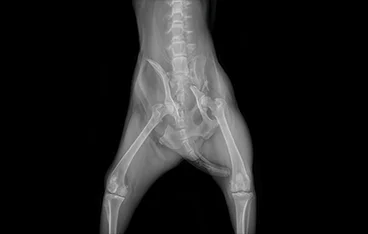

고관절 질환

THR, FHNO, Toggle pin

• toggle pin 전

toggle pin 후